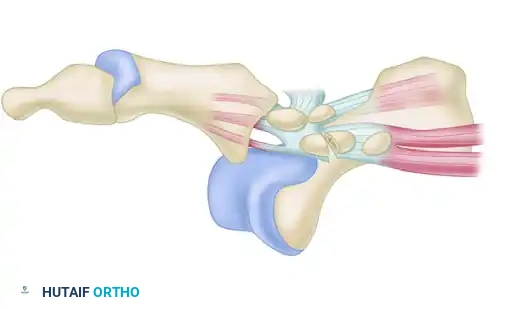

A profound understanding of the first MTP joint anatomy is non-negotiable for successful surgical reconstruction. The joint is a modified hinge joint, but its stability relies heavily on its soft-tissue envelope rather than its bony architecture.

FIGURE 88-78 A: Normal anatomy of the first metatarsophalangeal joint, demonstrating the relationship of the metatarsal head to the proximal phalanx and the underlying sesamoid complex.

The plantar plate is a thick, fibrocartilaginous structure that originates from the metatarsal neck and inserts firmly onto the plantar base of the proximal phalanx. Embedded within the flexor hallucis brevis (FHB) tendons are the medial (tibial) and lateral (fibular) sesamoids, which articulate with the plantar aspect of the first metatarsal head.

Clinical Pearl: The sesamoids function as a fulcrum, increasing the mechanical advantage of the FHB and protecting the flexor hallucis longus (FHL) tendon, which glides between them. The intersesamoid ligament connects the two sesamoids; its integrity dictates the reducibility of the dislocation.

The collateral ligament complex consists of the proper collateral ligaments (connecting the metatarsal head to the proximal phalanx) and the accessory collateral ligaments (connecting the metatarsal head to the plantar plate and sesamoids). Rupture or avulsion of these ligaments, particularly the tibial collateral ligament, is a hallmark of lateral or dorsal dislocations.